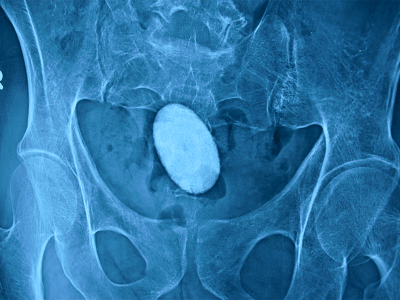

Bladder Stone

Urine contains many substances such as calcium, uric acid . If their concentration is more than normal , they can form crystals due to supersaturation. Initially they are like sandy particle . As time passes, more and more crystals get deposited on it and stone formation occurs.

1. Stone can be small, large, single or multiple.

2. They can be as big as a potato

3. They are hard in consistency, brown or black in colour

4. They can be round, oval, with smooth or irregular surface

A consultation with an experienced urologist is of utmost importance. It can be diagnosed by various method including x-ray and scan. Stone is removed by endoscopy procedure. Laser is used to remove large stones. The predisposing cause for the stone has to be treated to prevent recurrence of stones.